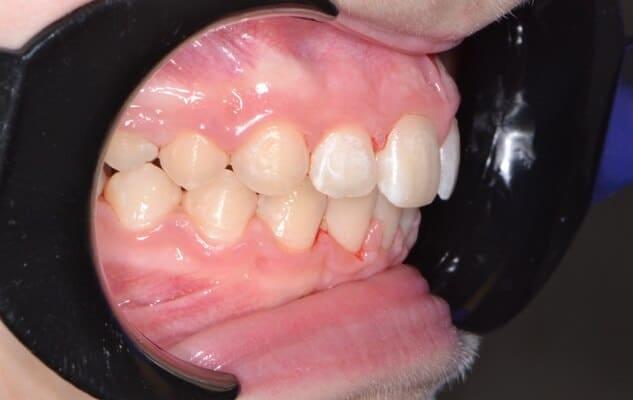

Дівчинка 2 років, але зуби вже мають глибокі ураження із залученням у запальний процес пульпи (“нерва”) зуба. На жаль, так трапляється і зволікати в такому випадку не можна. Було проведено лікування в умовах анестезіологічного забезпечення під контролем досвідченої анестезіологічної команди. Передні зубчики відновлено естетичними коронками, на жувальних зубчиках проведена герметизація фісур, а один вже має глибоке ураження карієсом, тому теж покритий коронкою. Одразу після лікування ясна можуть виглядати дещо травмованими, але за кілька днів вони повністю відновляться.